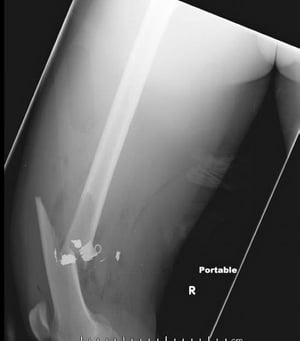

Frattura mediale della diafisi femorale (1)

Questa immagine mostra una frattura comminuta, angolata e accorciata mediale della diafisi femorale.

Image courtesy of Danielle Campagne, MD.

Frattura mediale della diafisi femorale (2)

Questa radiografia di profilo del femore mostra una frattura mediale della diafisi femorale con aria nei tessuti molli e corpi estranei di densità metallica trattenuti.

Questa radiografia di profilo del femore mostra una frattura mediale della diafisi femorale con aria nei tessuti molli

... maggiori informazioni